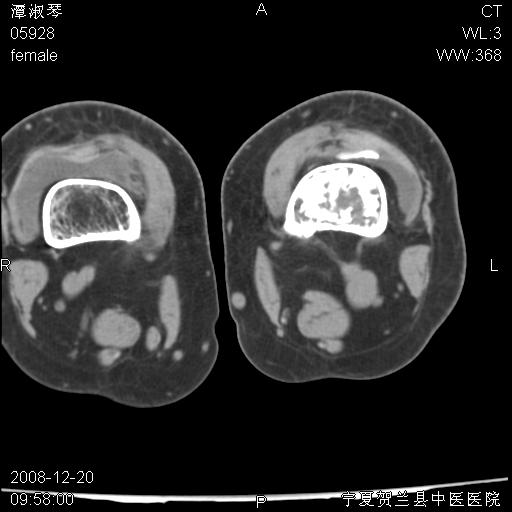

标题: CT17526:请各位看看是啥?

内生软骨瘤?骨梗死?

考虑内生软骨瘤可能性大

考虑-----骨梗死+退变

支持骨梗死,退行性骨关节病,膝关节积液.

考虑骨梗死可能性大

骨梗死可能性大

左股骨下段骨梗死。双膝退变。

左胫骨下端松质骨及髓腔内可见点片状高密度灶,骨皮质无明显膨胀及变薄。病变范围较长。支持骨梗死,退行性骨关节病,膝关节积液